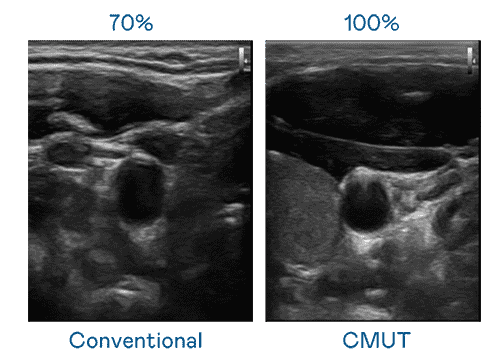

CMUT 技术是一种用电容式微机电元件来产生超音波讯号的技术。。。与传统 PZT 压电式技术相比,,,,CMUT 频宽增加 30%,,,更宽频的超音波讯号让影像解析度大幅提升,,,,是实现高影像品质医疗超音波扫描、、、、促进精准医疗发展的关键技术。。。

大频宽带来超清晰影像

超音波影像的解析度高低,,,首先取决于探头能发出的讯号频宽。。Wepay CMUT 可提供高清晰的超音波讯号,,提供高频宽、、、、高灵敏度、、、、影像纹理细节更高的超音波影像,,协助医护人员缩短影像判读时间及利用精准的医疗影像进行诊断。。。。